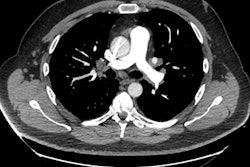

The diagnostic approach should be adjusted to whether GGO is acute (less thana few weeks) or chronic (more than six weeks). All images courtesy of Dr. Sebastian Röhrich et al.

Pathologies with GGO in a mid to lower distribution. The image is taken from acase of nonspecific interstitial pneumonia (NSIP). One of the most important locations to look at in a lower distribution of chronic GGO is the costophrenic angle, which may be involved (NSIP, desquamative interstitial pneumonia [DIP]) or spared (hypersensitivity pneumonitis [HP]).